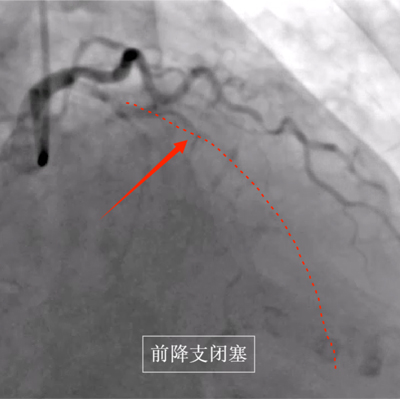

县人民医院为患者完善冠状动脉造影,提示前降支慢性闭塞,右冠极重度狭窄,相当于整个心脏供血均受影响,病情极其危险,随时可能再次出现生命危险 ,随后,心血管内科介入团队成功为其右冠快速并精准植入支架,解除患者右冠近端重度狭窄。手术后,患者的症状明显缓解,被安全送至心脏重症监护病房。